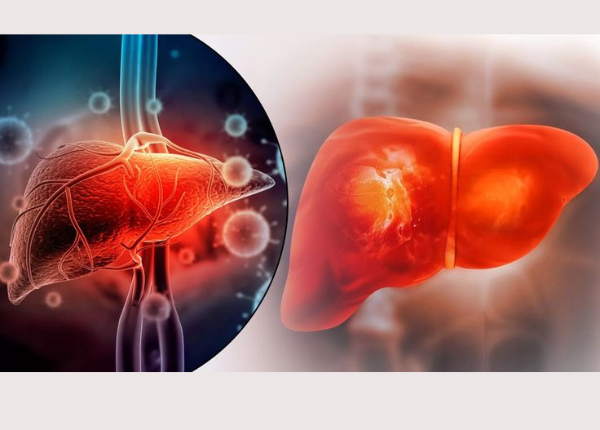

Bệnh gan có lây không và lây qua đường nào?

Nhiều người khi nghe chẩn đoán về các vấn đề liên quan đến gan thường lo lắng và đặt câu hỏi: bệnh gan có lây không? Thực tế, bệnh gan xuất phát từ virus và có khả năng truyền từ người này sang người khác, nhưng cũng có nhiều bệnh gan chỉ do lối sống ...

Bệnh viêm gan: Nguyên nhân và những lầm tưởng dễ mắc phải

Viêm gan là tình trạng viêm và tổn thương tế bào gan, làm suy giảm các chức năng quan trọng của gan như chuyển hóa, thải độc, dự trữ năng lượng và điều hòa hoạt động sinh lý toàn cơ thể. bệnh viêm gan có thể do nhiều nguyên nhân gây ra, bao gồm: nhiễm ...